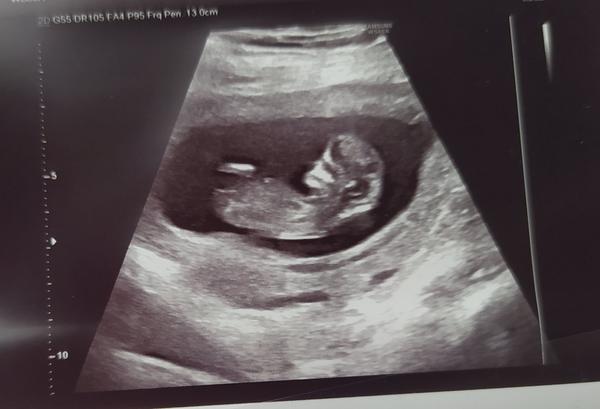

Pohlaví dle utz 14.tt. Nenapoví někdo?

Ahoj holky, sem stará a nedočkava 🙂 nenajde se některá, která má pohlavi z utz zmakle a nenapovi mi? Dekuji

na odpověď mas blbou fotku. Teda pěknou, ale z tyhle se to nepozna

@jijulka ja myslela podle hrbolku nebo co 🙂🙂

Tady s toho úhlu opravdu zadny hrbolek nejde vidět , to musí být hrbolek přímo mezi nožičkami , a mě doktor řekl že hrbolek směřuje náhodu 70% kluk ted 29 TT a je to kluk , u holek mi řekli že nejde nic vidět a pohlavo holčiček mi potvrdili až 22tt

@sabinakarlova Podle hrbolku sice ano, ale to by musel byt na te fotce videt.

Tady není hrbolek vidět, takže se to nedá poznat.